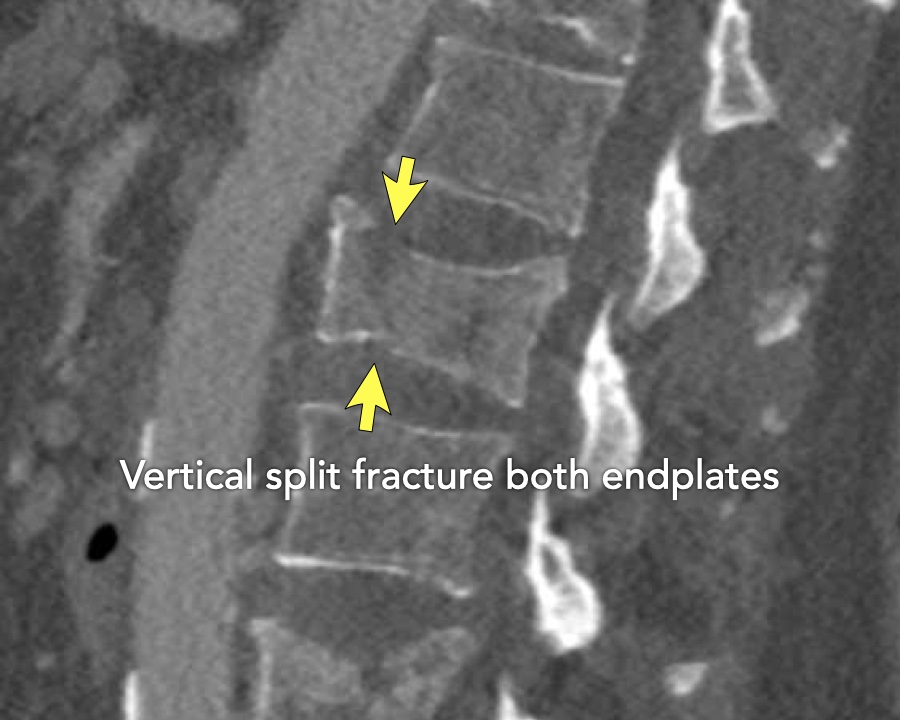

A2 Split fracture

A2 is a fracture of both endplates without involvement of the posterior wall of the vertebral body.

What is the highest AO-type of injury?

Findings:

- No C or B injury

- Fracture of the vertebral body with involvement of both endplates (1+1 points), no posterior wall involvement

Conclusion

injury type A2